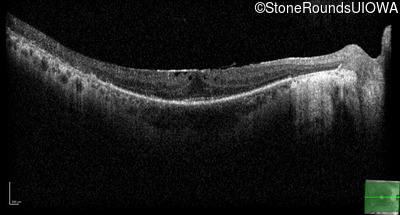

Optical Coherence Tomography - Right - 20/25 -2 sc

Exemplar / OCT Stack

OCT Stack